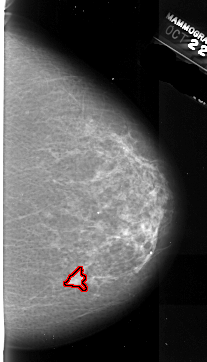

A_1008_1.LEFT_CC

FILE: A_1008_1.RIGHT_MLO.OVERLAY

TOTAL_ABNORMALITIES 1

ABNORMALITY 1

LESION_TYPE MASS SHAPE IRREGULAR MARGINS ILL_DEFINED

ASSESSMENT 4

SUBTLETY 4

PATHOLOGY MALIGNANT

TOTAL_OUTLINES 1

BOUNDARY